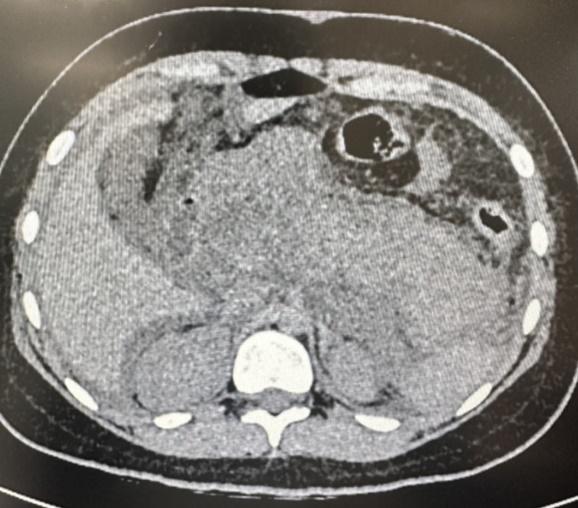

患儿小丽(化名)曾经患有“胆囊结石”,做过胆囊切除手术,近日因“剧烈腹痛4日”到上海儿童医学中心贵州医院就诊。接诊医生发现,小丽的腹肌紧张,呈板状腹,有明显腹膜炎体征;小丽的腹部CT提示有急性重症胰腺炎表现,血、尿淀粉酶均显著升高,病情危重。小丽因“急性重症胰腺炎合并脓毒性休克、多器官功能障碍”立即被收入重症监护室进行抢救。

CT显示小丽的胰腺肿胀明显,部分坏死,呈重症胰腺炎表现